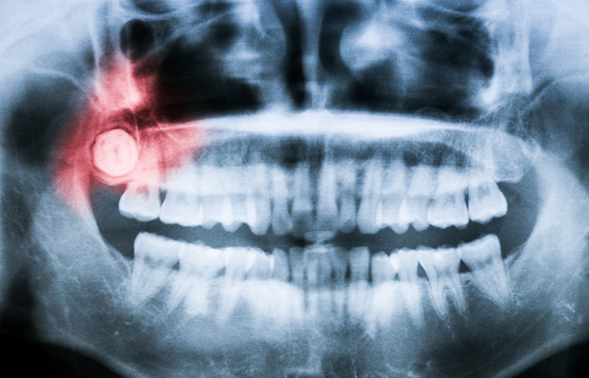

Impacted Wisdom Teeth

It’s relatively common for the wisdom teeth to become stuck while trying to come in, or impacted. In addition to causing pain in the back of the jaw, impacted wisdom teeth can also create a flap in the gum line that easily traps plaque and food particles, dramatically increasing a person’s risk for developing cavities. They often require a surgical extraction in order to be removed, and thankfully, our team has performed this kind of procedure countless times before.

In almost all cases, wisdom teeth are completely formed at 18 years of age. It is therefore recommended that the removal take place between the ages of 14 to 18. But not all cases are the same, and through further analysis, the right time would be determined on a patient-to-patient basis. Often, a general or family dentist will be the first to discover an issue with the wisdom teeth - typically through X-rays during routine dental checkups. During the extraction, a patient will be numbed with a local anesthetic, and then their doctor will remove any gum or bone tissue that is still encapsulating the tooth before removing the tooth itself. The treatment site would then be closed using self-dissolving stitches. Oftentimes, our patients opt to have the procedure performed while asleep under IV anesthesia for comfort.